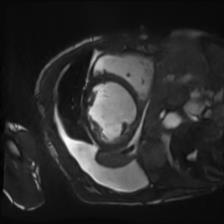

Recently, deep neural networks have greatly advanced undersampled Magnetic Resonance Image (MRI) reconstruction, wherein most studies follow the one-anatomy-one-network fashion, i.e., each expert network is trained and evaluated for a specific anatomy. Apart from inefficiency in training multiple independent models, such convention ignores the shared de-aliasing knowledge across various anatomies which can benefit each other. To explore the shared knowledge, one naive way is to combine all the data from various anatomies to train an all-round network. Unfortunately, despite the existence of the shared de-aliasing knowledge, we reveal that the exclusive knowledge across different anatomies can deteriorate specific reconstruction targets, yielding overall performance degradation. Observing this, in this study, we present a novel deep MRI reconstruction framework with both anatomy-shared and anatomy-specific parameterized learners, aiming to "seek common ground while reserving differences" across different anatomies.Particularly, the primary anatomy-shared learners are exposed to different anatomies to model flourishing shared knowledge, while the efficient anatomy-specific learners are trained with their target anatomy for exclusive knowledge. Four different implementations of anatomy-specific learners are presented and explored on the top of our framework in two MRI reconstruction networks. Comprehensive experiments on brain, knee and cardiac MRI datasets demonstrate that three of these learners are able to enhance reconstruction performance via multiple anatomy collaborative learning.